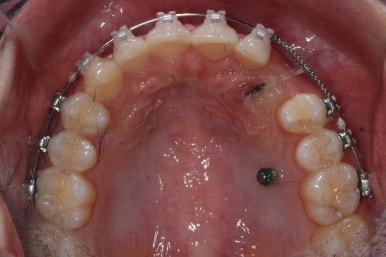

적절한 시기가 되면, 나머지 치아들을 가지런하게 할 준비를 합니다. 부산매복치아교정 키다리아저씨치과에서 이번에 사용한 장치는 클리피씨 입니다.

이번 환자분의 경우는 아랫니는 약간 삐뚤함이 있지만 굳이 교정치료를 원하지 않으셨기 때문에 윗니들만 부분교정으로 해결하기로 했습니다.

이상적으로라면 위-아래를 한 쌍으로 해야 교합을 맞추기에 유리하지만 이번의 경우는 윗니만 해도 충분히 교합을 맞출 수 있겠다고 판단하여 부분교정을 하였습니다.

부산매복치아교정 한 지 15개월만에 거의 제위치를 찾아가고 있는 모습입니다.

이번에도 매우 섬세한 조절을 위해 송곳니에는 철사가 두 줄로 연결되어 있기도 합니다.

어금니에는 일시적으로 치아를 띄워주기 위해 바이트레진이라는 것을 올리게 됩니다.

치아를 띄워주지 않으면 안쪽에 있던 송곳니를 바깥으로 데리고 나올 때 걸려서 못나오는 상황이 생길 수도 있기 때문입니다.